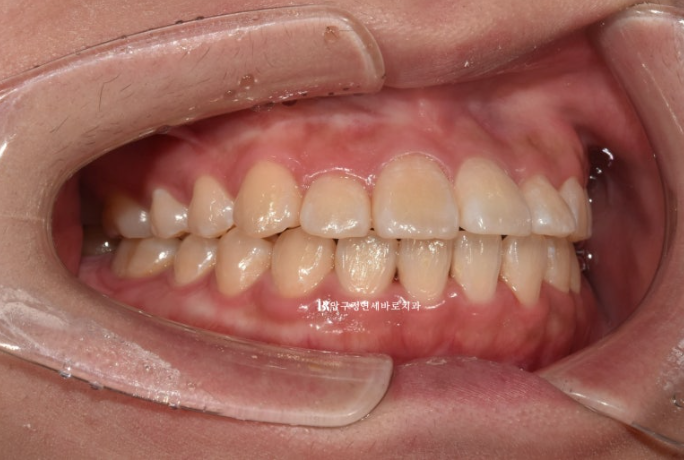

23.04

이 분은 치간삭제를 동반한 인비절라인라이트로 앞니 뻗침을 개선하기로 했습니다.

마침 앞니 사이즈가 큰 편이기도 하고 치근단 엑스레이상 치아의 최외곽층 에나멜 층도 평균보다 두꺼워서 어느정도 치간삭제를 해도 무리가 없는 상황이었기 때문입니다.